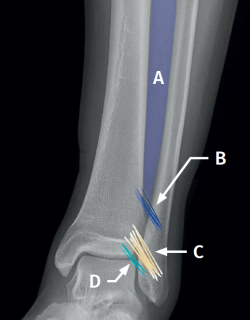

La técnica se realizará utilizando los portales anteromedial y anterolateral convencionales. El portal anteromedial se emplea para la visualización, mientras que el portal anterolateral sirve como portal de trabajo. Una vez visualizado el espacio tibioperoneo, resecaremos la sinovial inflamada con un shaver artroscópico para facilitar la reducción (Figura 7A). Posteriormente, mediante visión directa restauraremos el espacio tibioperoneo, teniendo muy en cuenta la posible malrotación del peroné, especialmente en fracturas de tipo Maisonneuve. Para la reducción peronea utilizamos una pinza de tipo Verbrugge que nos permite corregir la rotación. En nuestra experiencia, una vez limpiado el espacio y si la posición es correcta, es poco frecuente tener que utilizar una pinza compresora entre tibia y peroné.

Una vez obtenemos la reducción deseada, comprobamos mediante escopia la posición y fijamos temporalmente mediante una aguja de Kirschner la posición.

Para la fijación definitiva, las opciones quirúrgicas varían entre una fijación rígida con tornillos y una fijación dinámica. Los tornillos han sido el procedimiento estándar durante décadas, pero presentan complicaciones, como aflojamiento o rotura. Además, algunos cirujanos defienden su retirada, con el riesgo inherente de recurrencia de la inestabilidad(27). La fijación dinámica se diseñó para solventar algunos de estos problemas, al permitir cierto movimiento fisiológico de la sindesmosis, facilitar la carga temprana, reducir el riesgo de rotura y eliminar la necesidad de extraer el implante (Figura 7B).

Grassi et al., en un metaanálisis con más de 300 pacientes, demostraron una disminución global del riesgo relativo de complicaciones (RR = 0,55; p = 0,003) con sistemas dinámicos(28). Raeder et al., en un ensayo aleatorizado de 97 pacientes entre fijación con tornillos y sistema dinámico, demostraron una menor incidencia de artrosis con suture button del 65 vs. 35% (p = 0,009) a los 5 años(29). Las construcciones con suture button aportan cierto grado de micromovilidad, imitando la movilidad fisiológica, que puede favorecer la cicatrización ligamentosa. Asimismo, los implantes flexibles toleran mejor una reducción imperfecta, una complicación posible, aunque realicemos un control artroscópico de la articulación.

Figura 1. Esquema de la sindesmosis anterior. A: membrana interósea; B: ligamento interóseo; C: ligamento tibioperoneo anterior; D: fascículo distal del ligamento tibioperoneo anterior.

Figura 7. A: desbridamiento del espacio tibioperoneo; B: estabilización de la sindesmosis mediante sistema de suspensión.